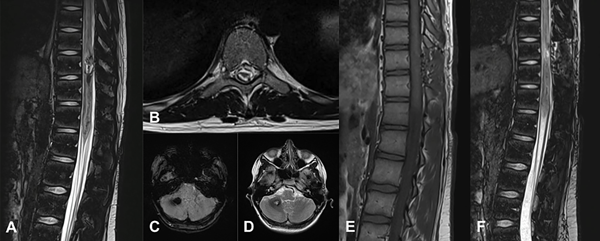

Figura 6. MC medular a nivel T10. Paciente masculino de 15 años que ingresa por paraplejía progresiva de varios días de evolución y compromiso de esfínteres. A) RM de columna dorsolumbar corte sagital T2-STIR que evidencia lesión heterogénea, compatible con MC. B) RM corte axial T2-STIR. C-D) RM de cerebro secuencias SWI y T2 que muestra otra lesión en hemisferio cerebeloso derecho. Por la severidad del cuadro clínico se realizó cirugía de urgencia. E-F) RM de columna dorsolumbar postquirúrgica, secuencias T1 y T2-STIR donde se observa el lecho quirúrgico libre de lesión. Se observa laminectomía del nivel T10. El paciente tuvo una recuperación parcial del foco neurológico. Actualmente en rehabilitación.

Manejo de lesiones espinales

Los cavernomas espinales corresponden al 5-12% de todas las anomalías vasculares en esta localización24,39 y representan el 6.5% de las MC del SNC.3 En la mayoría de los casos son lesiones intramedulares (55%),3,39 y pueden encontrarse con menor frecuencia de manera intradural extramedular (15%), epidural (20%) o vertebral (10%).3 Predominantemente se ubican a nivel torácico.3,9 Suelen ser lesiones esporádicas, pero se han descripto lesiones intracraneales asintomáticas con MC espinales sintomáticas. En la serie de Cohen Gadol y cols. de MC espinales, 42% presentó al menos una lesión intracraneal adicional.39 Por ello, a pesar de no poseer antecedentes familiares, se sugiere en estos casos realizar imagen completa del neuroeje.

El riesgo anual de sangrado se estima en 1.6%.3,39 Las MC espinales se manifiestan clínicamente alrededor de la tercera o cuarta década de la vida; su presentación y crecimiento durante la infancia son raros.28 En su curso clínico pueden presentarse como cuadros agudos mielopáticos (26-30%), con paraparesia/paraplejia y radiculopatía, como deterioro neurológico progresivo (41-54%), o como un deterioro neurológico escalonado (16-30% debido a los microsangrados reiterados).3,6,9

En las MC espinales sintomáticas, el tratamiento de elección es la exéresis completa con técnica microquirúrgica, de manera temprana, para lograr preservar la función neurológica.3,6,39 La cirugía puede tener morbilidad per se y la exéresis incompleta trae aparejado riesgo de resangrado, por lo cual no se recomienda de manera profiláctica. En casos donde la lesión no muestra expresión en la superficie medular puede ser de utilidad usar neuronavegador o ecografía intraoperatoria.3

En la serie de Gross y cols. se evidencia una mejoría de 61% de los pacientes luego de la resección quirúrgica, mientras que 27% permaneció igual y 12% tuvo deterioro en el seguimiento.20 En la serie de Sawarkar y cols., 67% mostró mejoría del déficit motor, sobre todo aquellos pacientes con instalación temprana del tratamiento; 17% no mejoró el déficit previo debido a sintomatología de largo tiempo de evolución y 17% presentó paraplejia postquirúrgica.6 Un 33% de los pacientes con déficit sensitivo y esfinteriano mejoró dichos síntomas. El dolor neuropático posterior a la hemorragia suele ser refractario al tratamiento quirúrgico.39

En nuestra serie presentamos un único caso de lesión espinal sintomática, con lesión intracraneal concomitante asintomática (ver Figura 6). El paciente se presentó con cuadro motor de más de 72 horas de evolución, llegando a la consulta con paraplejia, nivel sensitivo y alteraciones esfinterianas. Se instauró tratamiento de exéresis total de urgencia, en concordancia con la bibliografía. Se obtuvo una recuperación motora parcial, requiere de ayuda para las actividades de la vida cotidiana, sin recuperación de sensibilidad ni esfínteres.